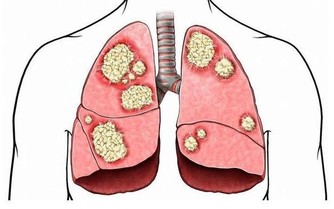

人體尿酸有兩種來源:一是內源性的,是有身體內的氨基酸、核酸等分解而代謝出來,約佔80%;二是外源性的,是有吃的食物中的核苷酸分解代謝而出,佔20%左右。

如果是原發性的高尿酸血症,採用低嘌呤的飲食,雖然可以降低尿酸水平,但是因為身體內已經含有大量的尿酸鹽沉積在關節腔內,必須用藥無治療才能降低尿酸的水平,